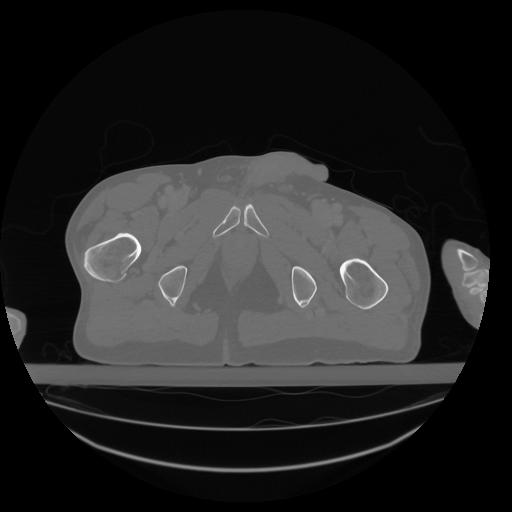

34 CUERPO,CE,Vol,1.0,CUERPO,,